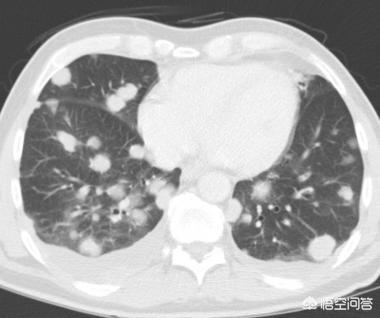

Par exemple, celle-ci, observée pendant 4 années consécutives, la masse n'a cessé de croître.